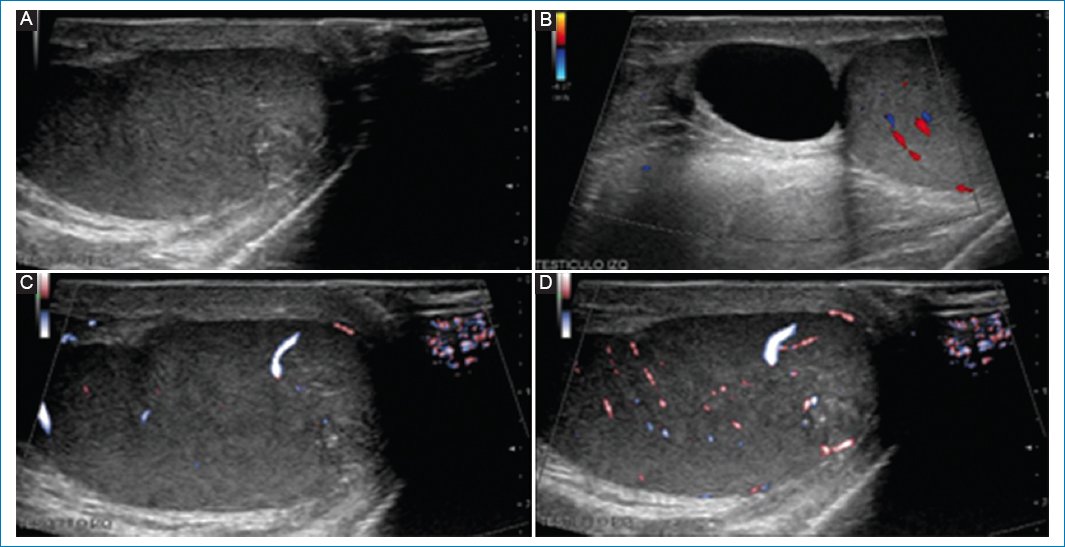

Acude a consulta de urología pediátrica paciente de sexo masculino de 14 años, previamente sano, quien identifica pequeña tumoración en polo superior del testículo izquierdo. A la exploración física únicamente se identifica una tumoración testicular de alrededor de 1.5 cm dependiente del epidídimo, por lo que se solicita estudio ultrasonográfico, el cual reporta quiste simple de epidídimo izquierdo de 18 × 15 mm de diámetro, correlacionando con la clínica del paciente; sin embargo, se notifica como hallazgo agregado imagen nodular heterogénea en polo inferior de testículo izquierdo, hipovascular (Fig. 1).

Figura 1. A: se observa imagen nodular heterogénea en polo inferior del testículo izquierdo. B: se identifica imagen anecoica, redondeada, bien delimitada, de 18.8 mm en la cabeza del epidídimo. C y D: se advierte vascularidad general conservada, la imagen nodular previamente descrita se aprecia con hipovascularidad.